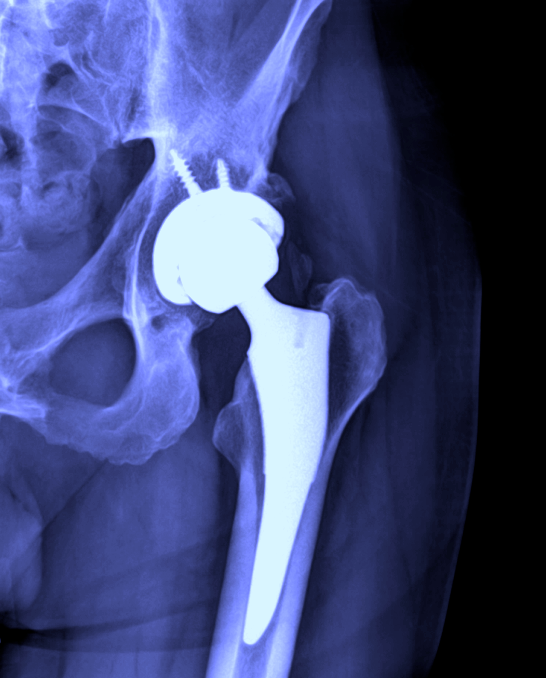

What Joints Can Be Replaced . Learn more about the different types of. Joint replacement surgery involves removing a damaged joint and replacing it with a new joint. Replacing a joint can relieve pain and help you move and. Other joints, such as the thumb, big toe, and finger joints can also be replaced when necessary. The doctor may suggest a joint replacement to improve how you live. Joint replacement surgeries can be of the hip, knee, shoulder, ankle, elbow and fingers. The knees, hips, ankles, shoulders, wrists, and elbows can all be replaced. The most common joints replaced are hip, knee, ankle, wrist, shoulder, and elbow. Surgeons can replace many joints, such as the: However, hip and knee replacements are considered the. The prosthesis is designed to replicate the movement of a normal, healthy joint. Total joint replacement is a surgical procedure in which parts of an arthritic or damaged joint are removed and replaced with a metal, plastic or ceramic device called a prosthesis.

Total joint replacement is a surgical procedure in which parts of an arthritic or damaged joint are removed and replaced with a metal, plastic or ceramic device called a prosthesis. However, hip and knee replacements are considered the. Joint replacement surgeries can be of the hip, knee, shoulder, ankle, elbow and fingers. Joint replacement surgery involves removing a damaged joint and replacing it with a new joint. The most common joints replaced are hip, knee, ankle, wrist, shoulder, and elbow. The prosthesis is designed to replicate the movement of a normal, healthy joint. Replacing a joint can relieve pain and help you move and. Surgeons can replace many joints, such as the: Learn more about the different types of. The knees, hips, ankles, shoulders, wrists, and elbows can all be replaced.

What Joints Can Be Replaced The prosthesis is designed to replicate the movement of a normal, healthy joint. Total joint replacement is a surgical procedure in which parts of an arthritic or damaged joint are removed and replaced with a metal, plastic or ceramic device called a prosthesis. Joint replacement surgeries can be of the hip, knee, shoulder, ankle, elbow and fingers. The most common joints replaced are hip, knee, ankle, wrist, shoulder, and elbow. Learn more about the different types of. Joint replacement surgery involves removing a damaged joint and replacing it with a new joint. The doctor may suggest a joint replacement to improve how you live. The prosthesis is designed to replicate the movement of a normal, healthy joint. However, hip and knee replacements are considered the. Replacing a joint can relieve pain and help you move and. Surgeons can replace many joints, such as the: Other joints, such as the thumb, big toe, and finger joints can also be replaced when necessary. The knees, hips, ankles, shoulders, wrists, and elbows can all be replaced.